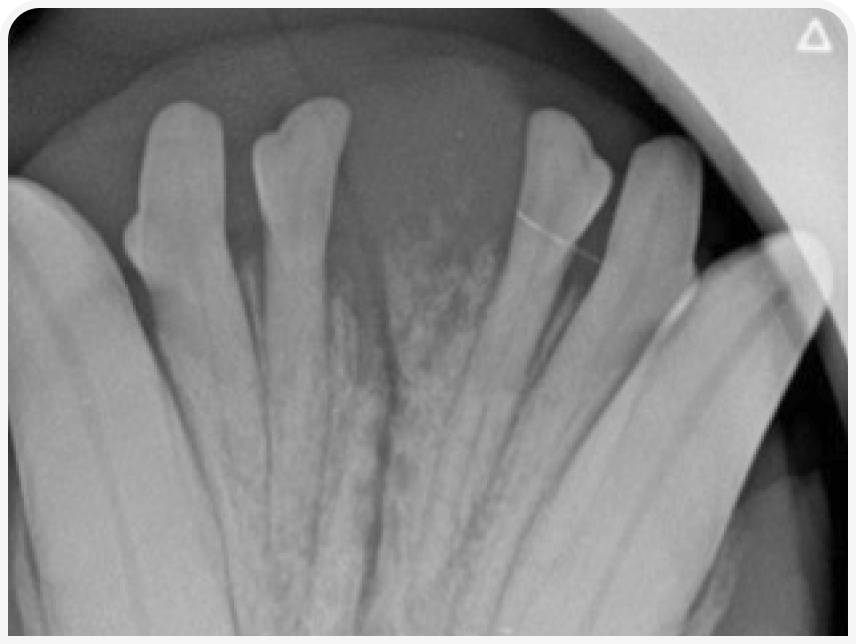

При диагностической визуализации (компьютерная томография или внутриротовая рентгенография) не должно быть видно лизиса кости, вызванного поражением (Рисунок 3), хотя возможна потеря костной массы пародонта, поскольку FEPLO/POF образует ложный карман.

Степень минерализации при FEPLO/POF может быть различной, могут образоваться цемент, кость или их комбинация. Доброкачественные новообразования, такие как FEPLO/POF, часто, хотя и не во всех случаях, вызывают смещение зубного ряда.